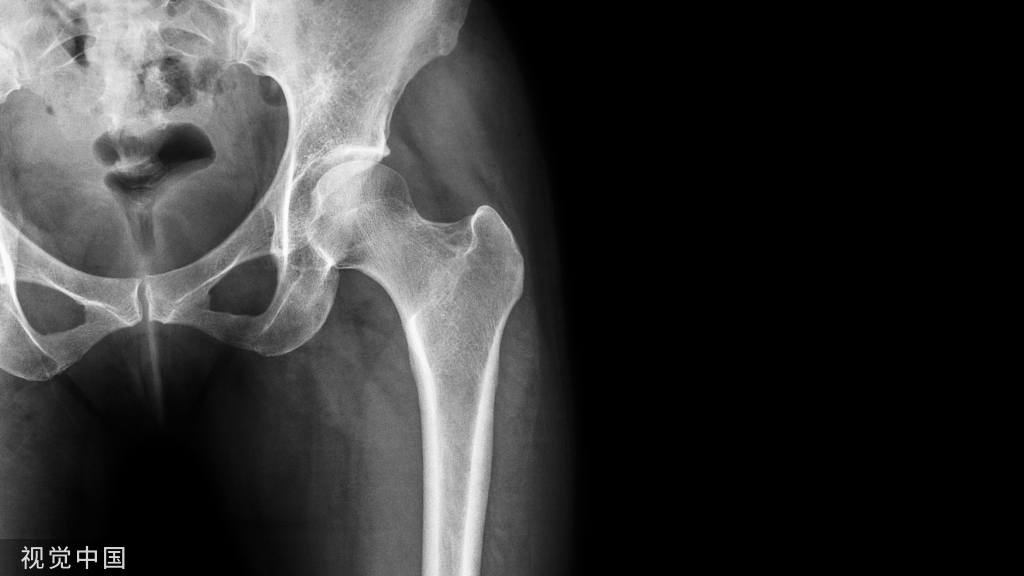

Tillaux骨折,指下胫腓前韧带在胫骨起点处发生的,累及胫骨远端骨骺的撕脱骨折。是一种多发于青少年的特殊类型骨折,约占所有胫骨远端骨骺损伤的 2.9%。最早由Cooper在1822年提出,之后法国医生Tillaux做了进一步解剖学试验并详细描述了这一骨折过程,将其命名为Tillaux骨折。常合并踝关节周围其他的骨折及韧带损伤。单纯的Tillaux骨折病例比较少见,多发生于未成年人,在成人中比较少见,加之单靠X片诊断较为困难,故常容易漏诊。一旦误诊或漏诊,延误治疗,有可能导致踝关节不匹配、不稳定,患者会遗留疼痛甚至发展为创伤性关节炎。

Tillaux骨折常为旋后外旋损伤所致,其发生机制是外旋应力作用在胫腓前韧带,造成胫骨远端前外侧骺板撕脱性损伤。这种骨折多发生在内侧的骺板已经闭合,但骺板的外侧尚未闭合的特定时期,也就是女性12~14岁,男性14~17岁期间,胫骨远端骨骺闭合的整个过程大约历时 18 个月,闭合的过程中,骺板的中央部分首先闭合,其次是前内侧,然后是内、后侧,最后是外侧。闭合和未闭合骨骺的强度不同,这是影响其骨折线走行模式的重要因素。